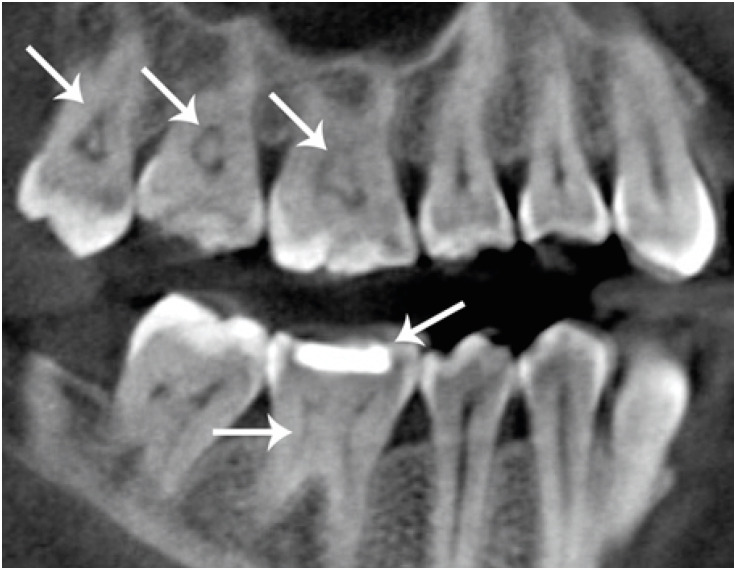

Figure 2

Sagittal cone-beam computed tomography section of maxillary molars with pulp stones and a mandibular first molar with a pulp stone and medium restoration.

The presence of pulp stones was investigated according to age, sex, dental type and location and the presence and type (composite or amalgam) of restorations. A pulp stone was considered a clear radiopaque mass (round or oval shape) in the coronal pulp chamber (Figures 1 and 2). The depths of the restorations (shallow: up to one-third of the dentin affected; medium: one-third to two-thirds of the dentin affected; deep: two-thirds to all of the dentin affected without exposure of pulp) were also recorded according to the method described by da Silva et al. [9] (Figures 2 and 3). All the restorations were assessed in the sagittal plane, and the deepest point of the restorations was recorded.